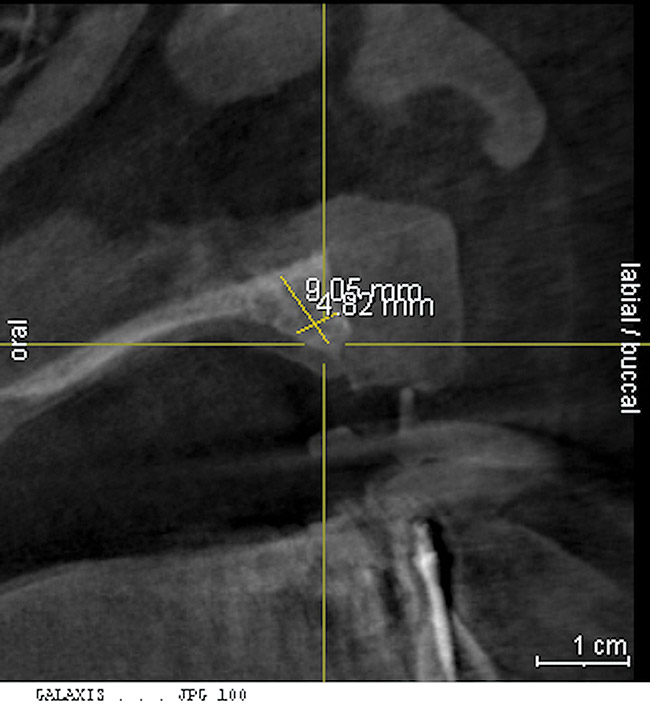

A 26-year-old woman presented with a history of trauma combined with an impacted maxillary right canine (No. 6), which was extracted in early childhood. Following two courses of orthodontic therapy—one in her early teens and the second in early adulthood—the area had reportedly been grafted approximately 9 months prior to her initial presentation to the author’s private periodontal practice. Clinically, the edentulous site appeared healthy, with significant keratinized mucosa in the canine position (Figure 1). A cone-beam CT scan revealed severe horizontal bone deficiency in the proposed implant position (Figure 2). Adequate bone height for implant placement was evident; however, the thinnest portion of the ridge measured approximately 0.45 mm in width. It was proposed that an augmentation be performed to facilitate implant placement, which the patient accepted.

Approximately 4 months after grafting, the patient returned for clinical and 3-D radiographic evaluation. The thinnest area of ridge width preoperatively was remeasured in approximately the same location, demonstrating a gain of about 4 mm (Figure 7). The treatment plan was to place a 3.5-mm x 13-mm implant with a computer-generated guide (SiCat, Sirona Dental, www.sironausa.com), eliminating an additional open surgical procedure. Planning included initial osteotomy preparation with single-use drills combined with a localized ridge expansion using narrow, tapered osteotomes. This was performed approximately 5 months after the augmentation procedure, achieving primary stability of the implant, facilitating a transmucosal healing approach (Figure 8 and Figure 9). Following each step of osteotomy preparation, a probe was inserted along the walls of the site to confirm the integrity of the buccal and palatal walls prior to implant insertion.

Figure 2 Cone-beam CT scan revealed severe horizontal bone deficiency in the proposed implant position.

Figure 2

Figure 7  3-D radiographic evaluation showed a gain of about 4 mm in the thinnest area of ridge width.

Figure 7